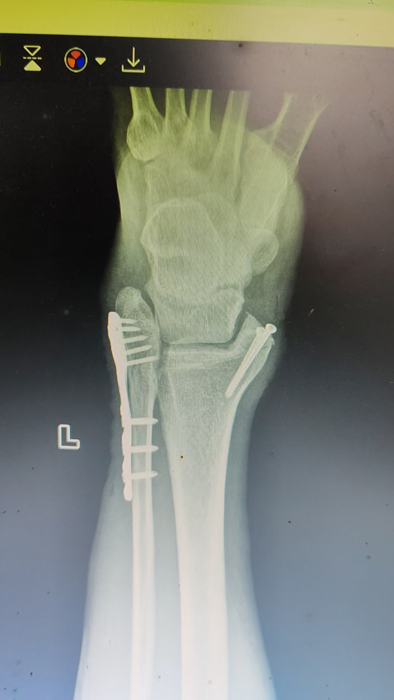

2月4日,何店鎮(zhèn)中心衛(wèi)生院接診一名左踝關(guān)節(jié)外傷患者,經(jīng)影像檢查,確診為左脛、腓骨下段骨折。外科醫(yī)生姜穩(wěn)迅速完成術(shù)前檢查及病情評估,并與患者及家屬深入溝通治療方案。在患者強烈要求于本院進行手術(shù)的情況下,為最大限度保障手術(shù)質(zhì)量與安全,該院特邀請醫(yī)共體牽頭單位——曾都區(qū)人民醫(yī)院脊柱創(chuàng)傷外科專家團隊前來指導(dǎo)。

本次幫扶由曾都區(qū)人民醫(yī)院脊柱創(chuàng)傷神經(jīng)外科主任徐三軍帶隊,專家團隊抵達后立即完成手術(shù)風險評估及術(shù)前準備。手術(shù)過程中,徐三軍主任嚴格規(guī)范完成各項手術(shù)操作,并同步結(jié)合手術(shù)步驟,為該院外科醫(yī)師詳細講解骨折手術(shù)的關(guān)鍵要點、操作技巧、術(shù)中注意事項及術(shù)后康復(fù)要領(lǐng)。通過“手把手”的實戰(zhàn)帶教,專家將豐富的手術(shù)經(jīng)驗與規(guī)范的診療思路傾囊相授,讓該院醫(yī)護人員在實操中學(xué)習(xí),在過程中成長。